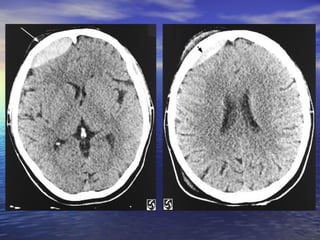

• #17 Slide #16 Subdural Hematoma Case: A 26 yo female presents to her family practice physician complaining of a headache that has persisted for over one month and sporadic blurry vision that has worsened over the last week. The headache is only slightly relieved with Ibuprofen and is worse when doing strenuous activity. The blurry vision comes and goes and can last minutes to hours when it is present. The neurologic and physical exams are normal except for some slight papilledema. The patient was then sent for a CT exam, the results of which are shown here. Diagnosis: Subdural Hematoma

• #18 Slide #17 Axial CT images of the brain show a large isodense right-sided subdural hematoma ( short arrows ) extending from the high convexities to the low frontal lobe. It is producing extensive right to left midline shift with subfalcine ( arrow )

• #19 Slide #18 and right uncal (arrow) herniation. There is trapping of the ventricles and left temporal horn with acute ependymal cerebrospinal fluid seepage, predominantly in the left periatrial and occipital regions (long arrow).

• #20 Slide #19 Subdural Hematoma